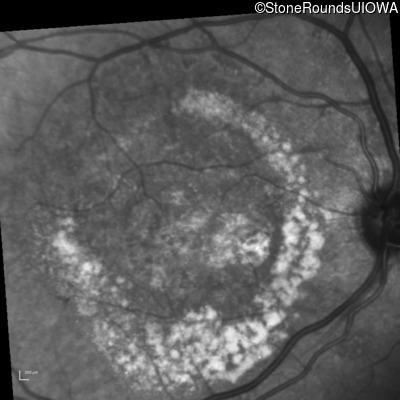

Fluorescein Angiography - Right - 20/250

Exemplar